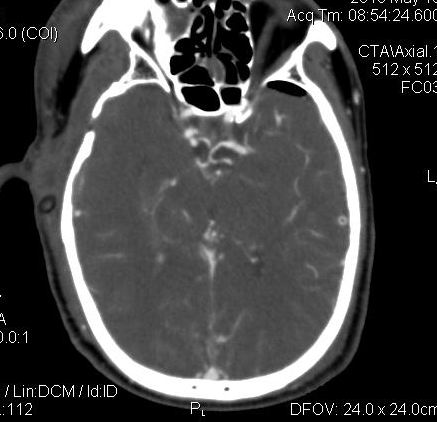

男.60岁,渐进性意识不清,ct检查双侧额颞顶部硬膜下血肿,开颅术后行脑血管cta,大脑中动脉起始部见一瘤状血管扩张。请各位老师留下宝贵意见

太常见了,报动脉瘤就可以

符合动脉瘤表现。

符合动脉瘤表现。

动脉瘤。

颅内动脉瘤。

后重建做得不是很好看,要将维蒂斯环充分显示,最好在增加一个mip。这样不好定位。

小动脉瘤

典型

符合动脉瘤的表现

动脉瘤

符合动脉瘤表现。

小动脉瘤

典型